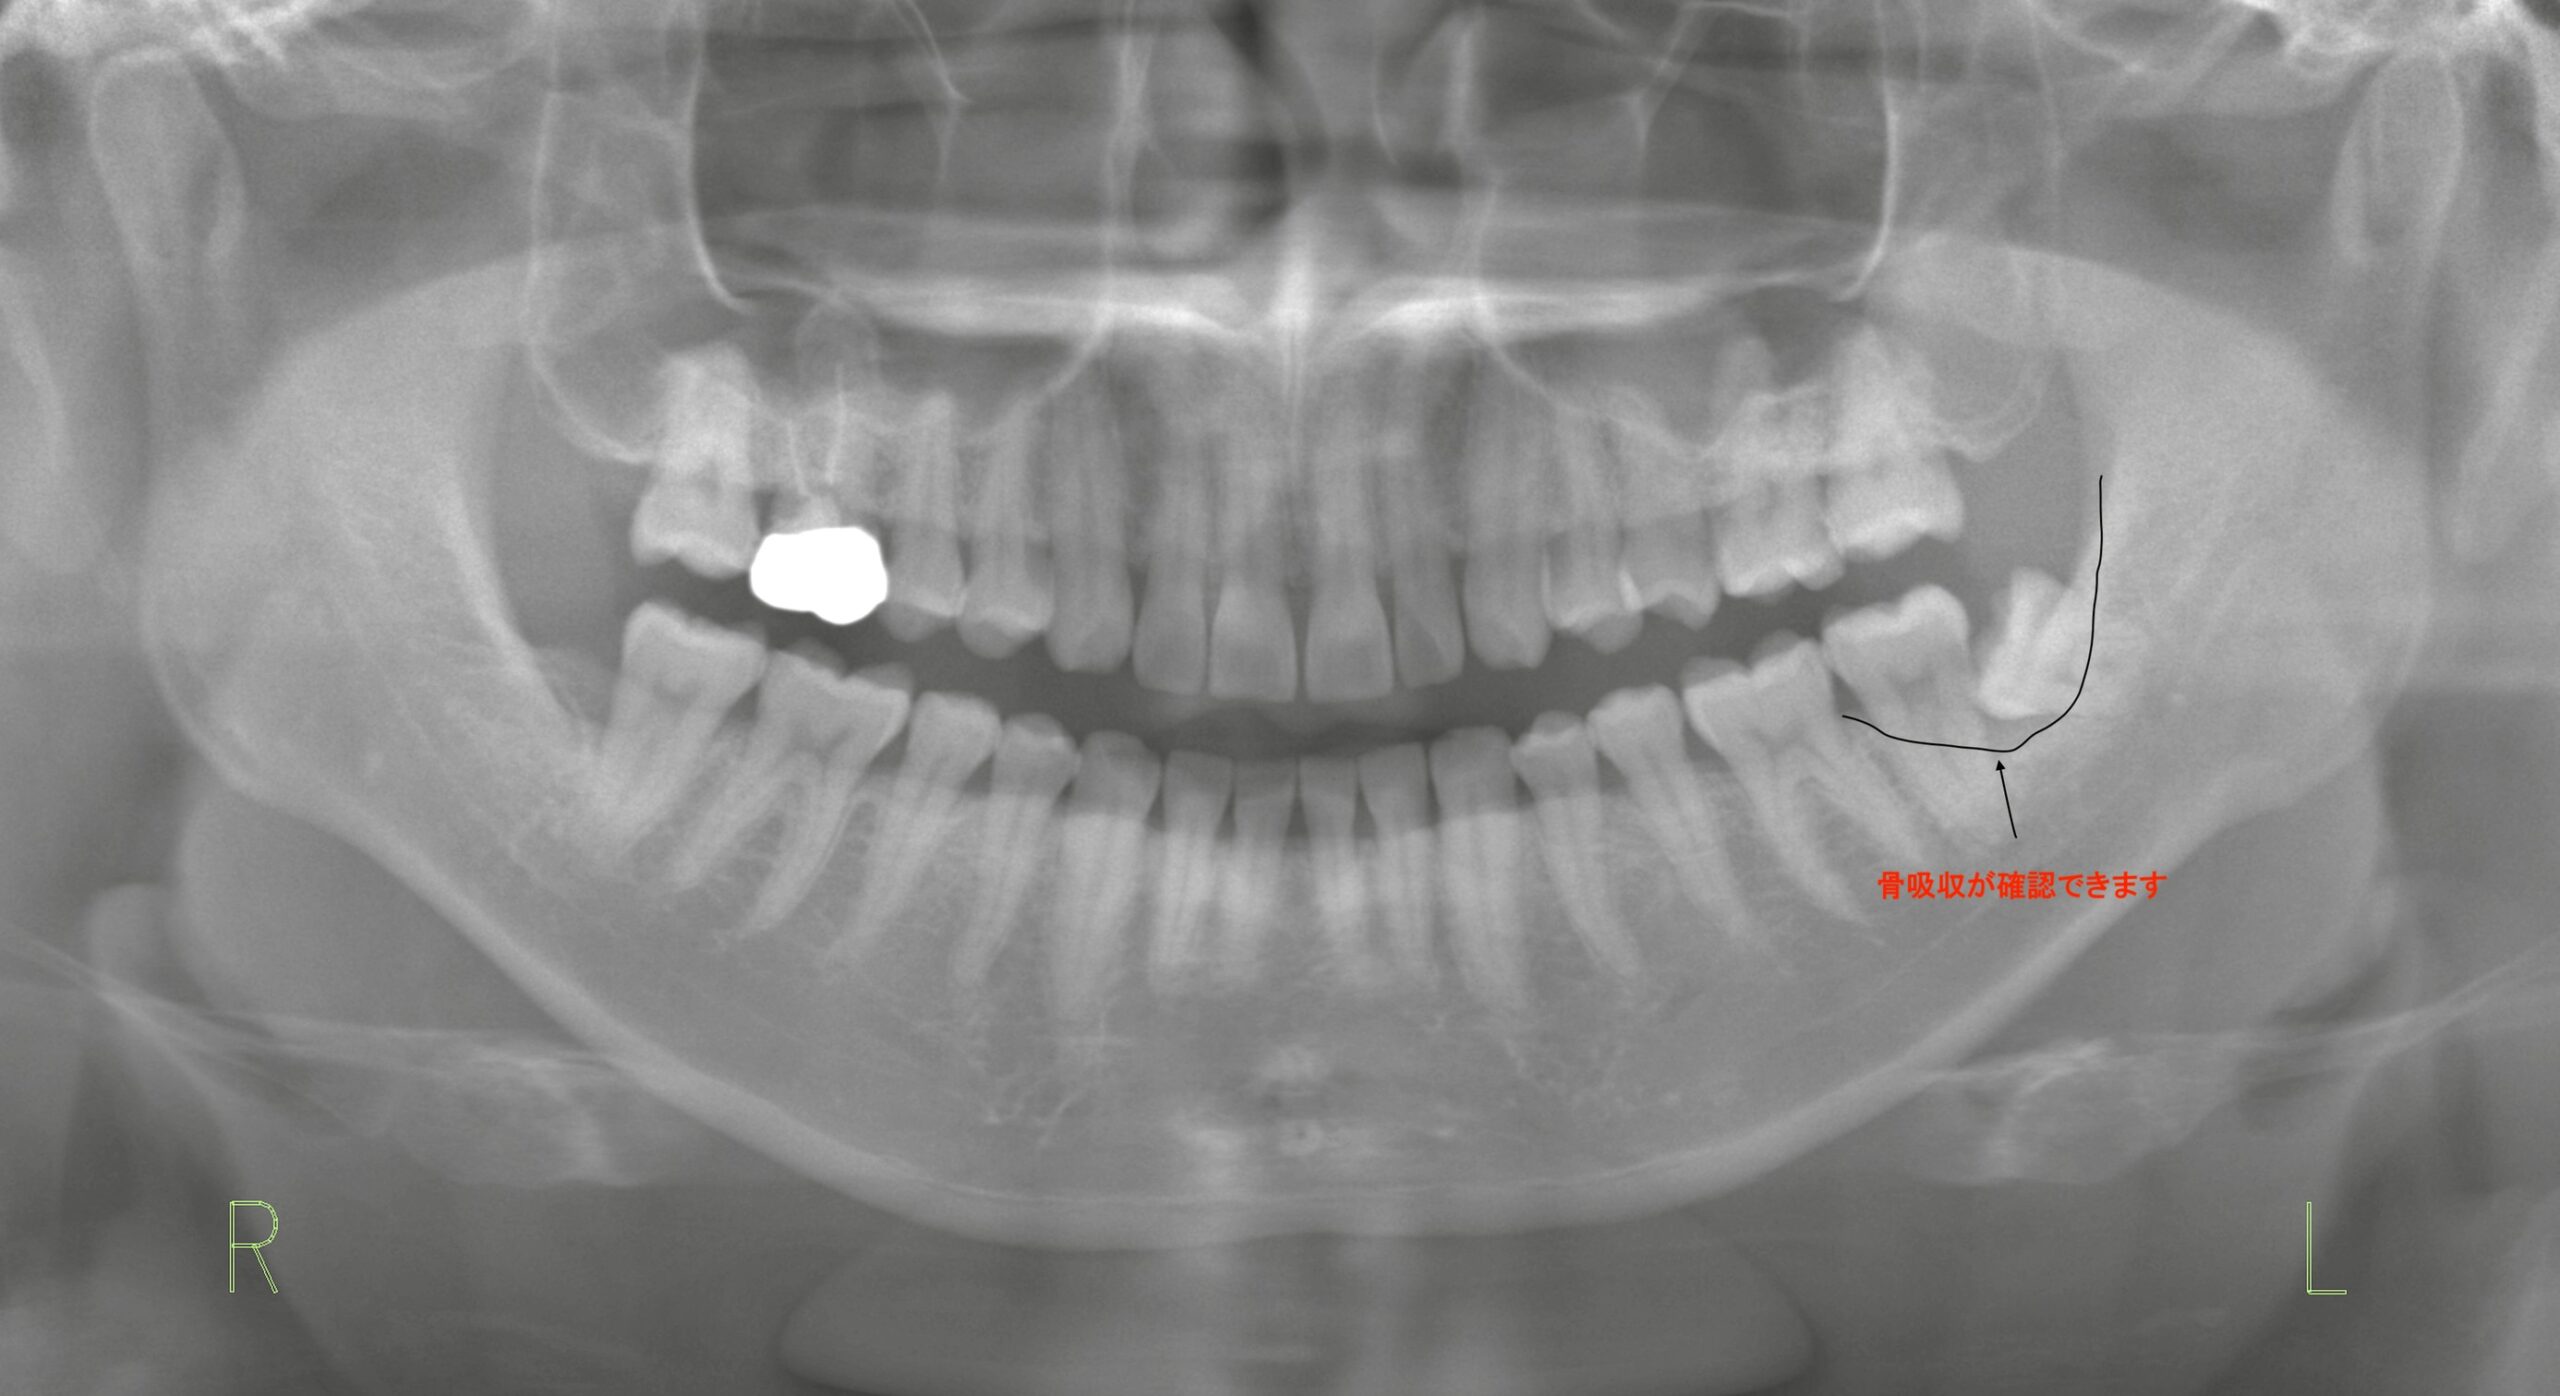

左下の親知らずの違和感と痛みを訴えて来院された患者様のケースをご紹介します。

親知らず(第三大臼歯)に隣接する第二大臼歯の骨が吸収されているのが確認できます。

これは、横向きに生えている親知らずによって清掃が難しくなり、歯周病が進行した結果と考えられます。

特にこのように中途半端に埋伏している親知らずは、磨き残しが多くなることによるリスクが非常に高いのです。